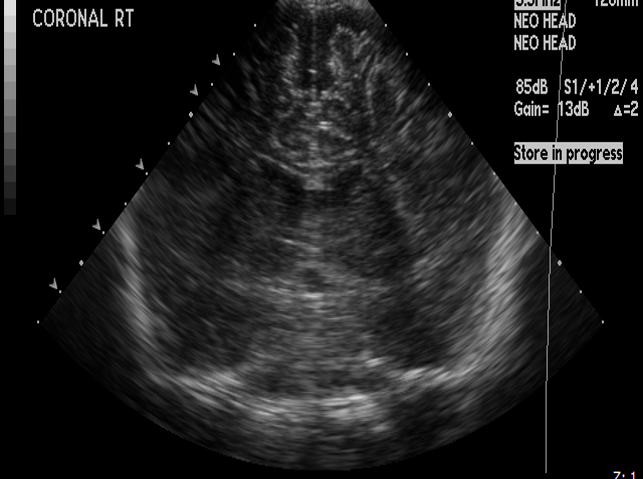

CSF spaces/ventricular system

There is prominence of the ventricular system. [Yes/No]

The lateral ventricle/s are dilated. [Yes/No]

The third ventricle is dilated. [Yes/No]

The 4th ventricle is dilated. [Yes/No]